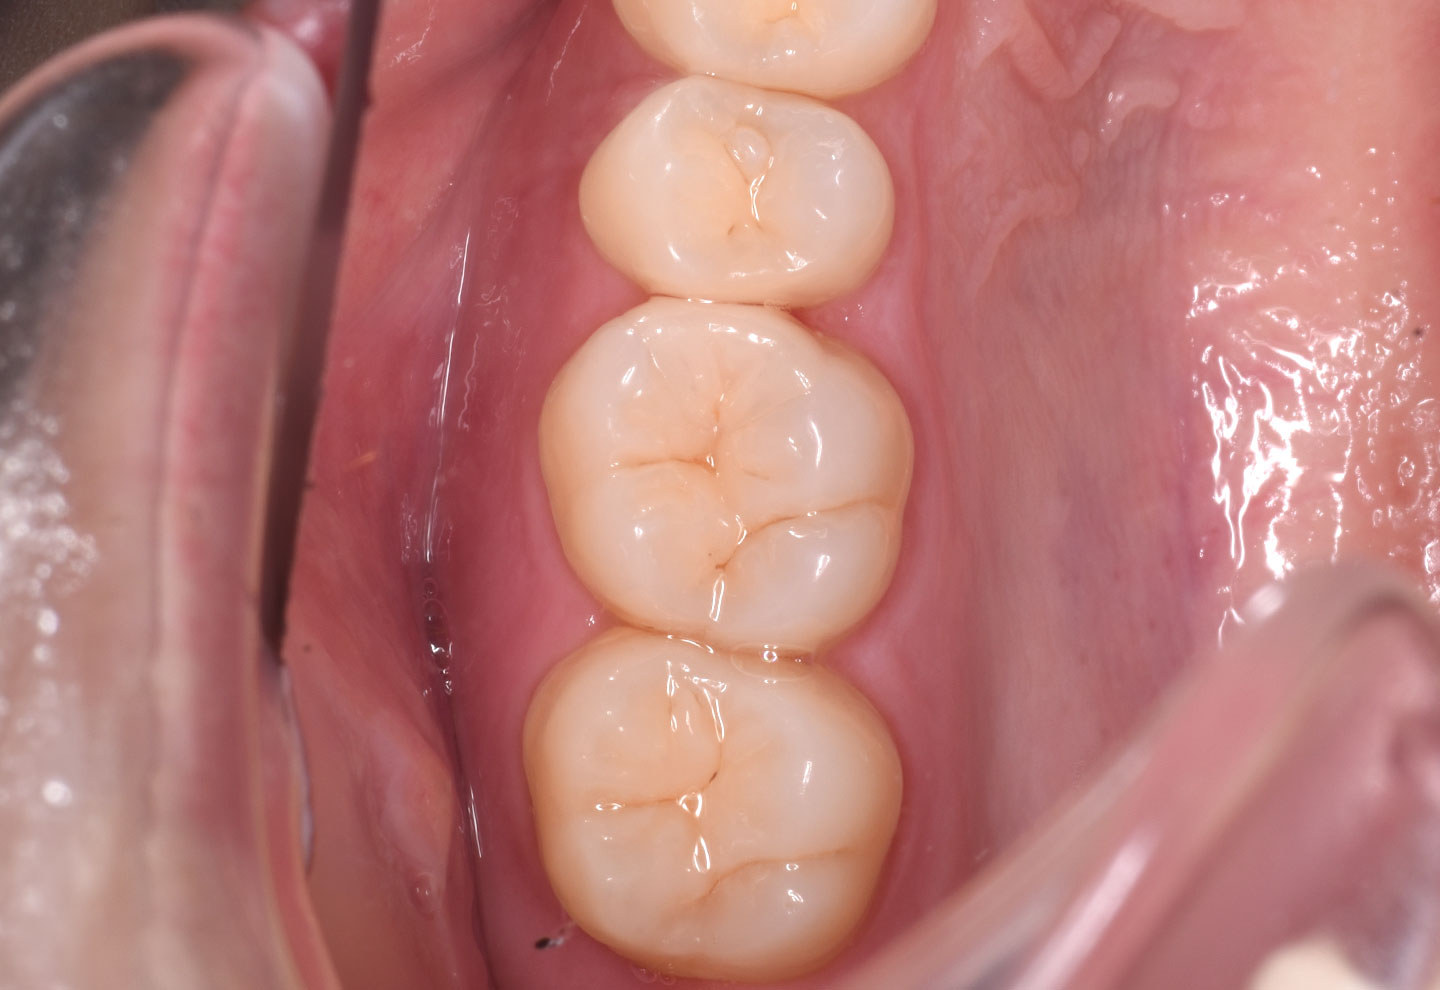

当院ではラバーダム防湿、IDS(象牙質即時封鎖)、多段階の接着プロトコルなど、精密な接着操作を徹底しています。

セラミック治療の接着精度を高める重要な工程です。

IDS(象牙質即時封鎖)は、歯を削った直後に象牙質を接着材で保護する処置です。

接着強度の向上や細菌侵入の抑制などの観点から、海外の研究や論文でも重要性が示されており、長期安定に寄与すると考えられています。

当院では、こうした学術的な知見に基づき、長く機能する修復治療を前提に接着工程を大切にしています。